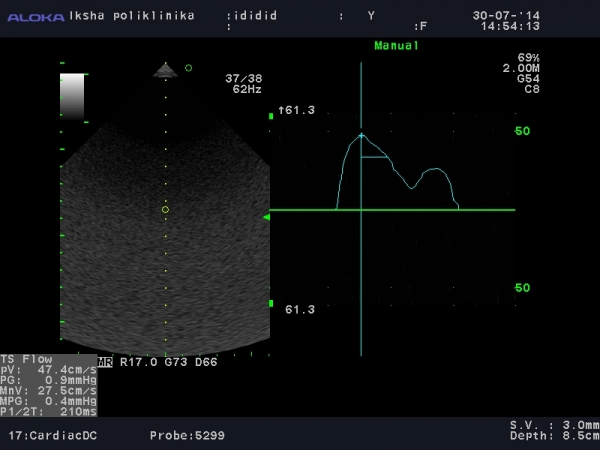

Прикрепляю две картинки. На них видно что умеет мой софт для трикуспидального:

Спасибо, это стандартные измерения на трикуспидальном клапане.

Но мой врач, считает что необходимо мерить поток на трикуспидальном как на митральном.